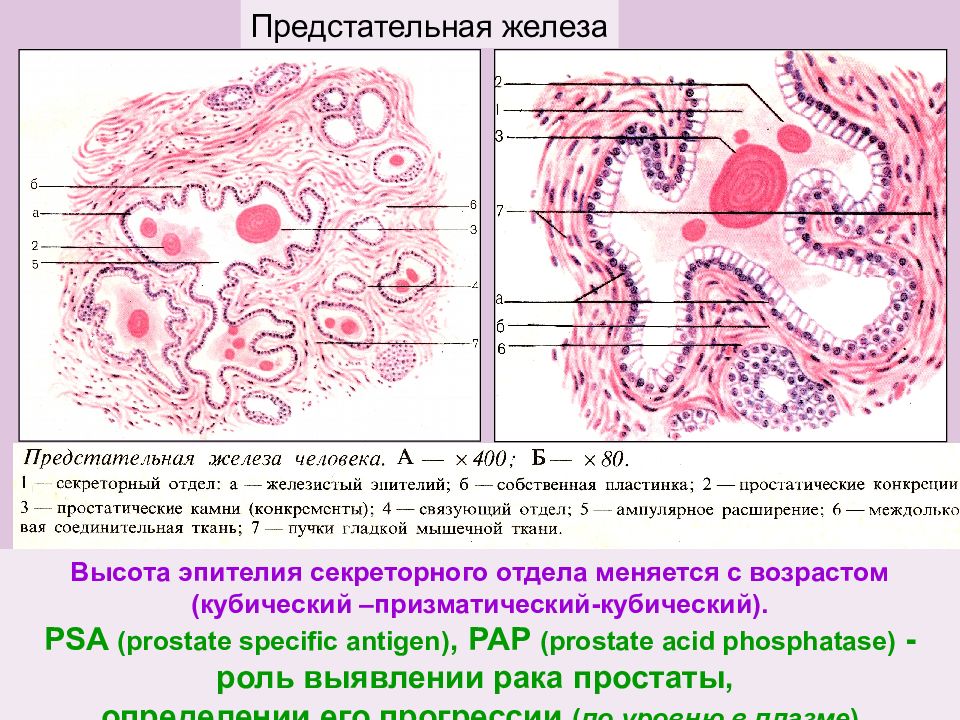

Простата детей